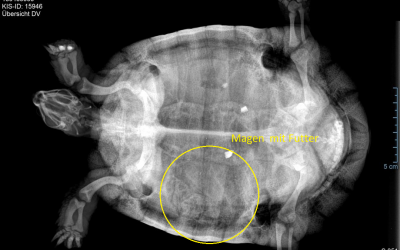

Immer wieder im Mai-Schildkröte PHA

Ich sag immer…